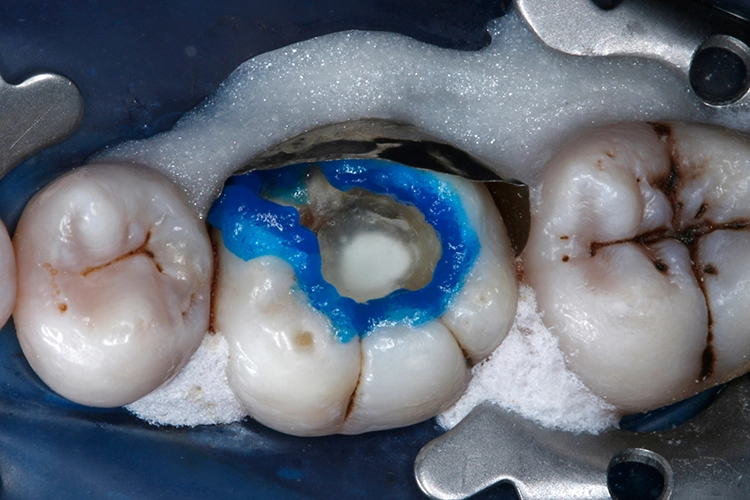

Anschließend wurden sämtliche Kavitätenränder mit einem Feinkorndiamanten nachgearbeitet und finiert. Danach wurden die pulpanahen Kavitätenareale mit einem selbstlimitierenden Polymer-Rosenbohrer (Polybur, Gebr. Brasseler GmbH & Co. KG, Lemgo) substanzschonend exkaviert (Abb. 7), eine Exposition der Pulpa konnte mit diesem Vorgehen der selektiven Exkavation vermieden werden (Abb. 8) [51–55]. Das pulpanahe Dentin im Zentrum der Kavität wurde mit einer dünnen Schicht röntgenopaker Calciumhydroxidpaste auf wässriger Basis (Calcicur, VOCO) indirekt überkappt (Abb. 9). Das Calciumhydroxidpräparat wurde mit einer partiellen Unterfüllung aus lichthärtendem kunststoffmodifiziertem Glasionomerzement (Ionoseal, VOCO) abgedeckt (Abb. 10).

Hierzu wurde 35%ige Phosphorsäure (Vococid, VOCO) zirkulär entlang der Schmelzränder aufgetragen und wirkte dort für 30 Sek. ein (Abb. 12). Anschließend wurden die Säure und die damit aus der Zahnhartsubstanz herausgelösten Bestandteile gründlich mit dem Druckluft-Wasser-Spray für 20 Sek. abgesprüht und anschließend überschüssiges Wasser vorsichtig mit Druckluft aus der Kavität verblasen. Nachfolgend wurde eine reichliche Menge des Universalhaftvermittlers Futurabond U mit einem Microbrush auf Schmelz und Dentin appliziert (Abb. 13).